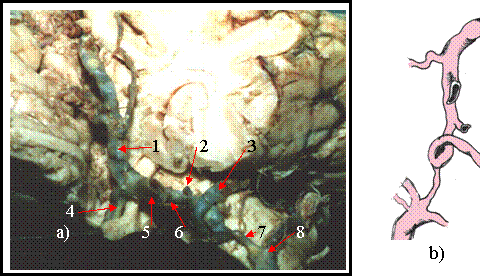

Cazul 9 [figura 9.9 a) si b) ]

In sectorul anterior al poligonului acestui caz se realizeaza un adevarat nod vascular la nivelul arterei comunicante anterioare.

Segmentele A-1 ale ambelor artere cerebrale anterioare se bifurca. Din segmentul A-1 din dreapta se formeaza segmentul A-2 al arterei cerebrale anterioare drepte si artera cerebrala mediana. Segmentul A-1 din stanga se bifurca intr-o ramura laterala - segmentul A-2 al cerebralei anterioare stangi si o ramura mediala ce se anastomozeaza cu potiunea initiala a arterei cerebrale mediane si reprezinta prima artera comunicantaanterioara. Intre cerebrala anterioara mediana si segmentul A-2 al cerebralei anterioare stangi mai exista doua

Figura 9.9 a) vasele poligonului Willis disecate pe encefal

b) prezentare schematica

1-segmentul A-2 al arterei cerebrale anterioare drepte. 2- artera cerebrala anterioara mediana. 3- artere comunicante si butoniere vasculare. 4- segmentul A-2 al arterei cerebrale anterioare stangi. 5- prima artera comunicanta anterioara.

comunicante, prezentand aspectul de anastomoze cu dispozitie scalariforma. Arterele comunicante posterioare bilateral sunt lungi sinuoase si subtiri, debitul sanguin dominant in cerebralele posterioare apartine trunchiului arterial bazilar..